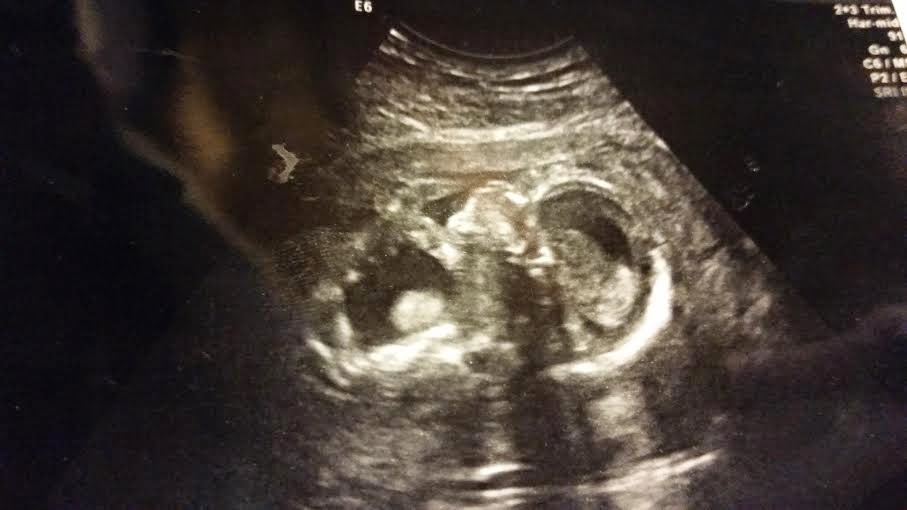

So off to Dr. Vick's office we went. Abel was still in there growing like a healthy little baby, just not peeing. His bladder was still very large, in fact it was larger.  Dr. Vick came in for a minute and about the same time he came in we saw Abel swallow!We actually saw him swallow a couple of times! This is apparently a great big good sign!!!! By Abel swallowing it show that his brain development was good.  Swallowing takes lots of brain function and muscles. This was a big deal in Dr. Vick’s eyes! As big people in the world I feel like we forget all the small mile stones we have to learn and over come to make it, like swallowing or even blowing your nose. We learn these things and they then become like second nature. From what our sonogram could also show it also looked like Abel’s kidneys still had good blood flow.  That meant they were still functioning. This was also another plus. Dr. Vick also believed that the kidneys were still producing urine because the bladder was larger- only way to get more pee in the bladder. Abel could swallow which also means he was trying to learn to breath. He was trying to develop like he needed to.

We got an appointment at Ft. Sanders with Dr. Roussis later that week. Victor wasn't sure he would make it to the beginning of the appointment, so I asked my dad to go with me. Like I said I have learned the hard way and did not plan on being at any doctor’s appointment by myself especially considering the circumstances. I am glad my dad got to come; he hadn't had the privilege of seeing our baby during a sonogram yet. Victor did make it for the entire appointment though and dad stayed. There is a comfort having a parent there, no matter how old you are. Dr. Roussis’ office was hands down wonderful! They took us back for a sonogram and we had two sonogram ladies.

They talked to us while they did their best to get good pictures of our baby. They answered my questions, not that I had a lot but I knew a few things to look for and ask about. They talked to us and told us what they were seeing. They pointed out Abel’s body parts and let us enjoy our baby on the screen as much as possible. (Check out that big ol' head, it's a Godwin head for sure because we can be notorious for that) After they got their pictures I got scooted off to the little consult room.

So on with the sonogram. The sonogram lady said she still saw a lot of fluid in the baby and his bladder was still large if not larger. So she did her thing and then went to get the doctors. Again the whole team came in… still no answers. All the blood test they did to test me for any infection under the moon all came back negative. They saw this as a good thing but still no answers why or how the Hydrops was caused. The bladder was still enlarged and the keyhole was more evident, there were still no answers to why or how to correct it. The amniotic fluid around the baby was still very low.  They still did not believe this was a chromosome issue they just didn't know what it was. There was not a lot of amniotic fluid around the baby to test for chromosomes at this point either. There was an option to tap the baby’s bladder and test those chromosomes but they didn't feel that was going to provide real answers either and again they didn't think this was a chromosome thing. They thought it was more developmental. And they didn't want to put me in any additional risk or the baby if it wasn't needed.

Our appointment was at 11 but the doctor’s office was swamped that day. I seriously don’t think we even got back to the sonogram until like 12. This sonogram was just different from right off the bat. I didn't see the baby moving quite as much as we had in the past. Previous visits it waved, rolled almost did tricks, this visit the baby wasn't so active. We heard a heart beat so everything has to be o.k, right? I thought well maybe the baby is getting bigger and room in there is tight. I mean I was 17 weeks but not looking very big. Some days I felt like I had more of a baby bump than others, some days I just looked like I ate a lot. Any ways, the lady that does our sonograms is one of the sweetest ladies ever, her name is Tina.  She has always done her best to help us get good pictures of our sweet baby. Our appointments have always been fun and exciting, why would this one be any different? Tina would always tell us what we were looking at and explain these crazy black and white images to us as she did her job. However, today she was quite. Josiah even looked kinda bored in this appointment. Tina wasn't talking much, I kinda just coughed it up to the fact the office was so busy and crazy and she was behind on schedule.  She said she was going to take some measurements and check some stuff out but as she looked at things she didn’t say much. Amy, who is the nurse practitioner, came in for a minute just to say Hi. When she left Tina said she had to go to the bathroom and she would be right back to get some profile pictures. Tina came back gave us a picture or 2 and sent us on our way. We walked out of this room into the other room where we usually talk to the doctor about everything. I told Victor something was off, Tina was off today. He told me not to worry. Then I saw Amy, Tina and another nurse come out of the sonogram room. I told Victor something was wrong, he told me not to be crazy or worry. I hoped I was just being over paranoid.

So we get to UT Medical and they do their own sonogram. Like I said I didn't realize the severity of what was going on and I don’t think Victor fully did either. Victor is more a worse case scenario kind of guy and I am more good things will happen kind of gal. Well it hit during the sonogram and it hit harder than a 100 pound brick. The sonogram lady said “oh that’s good I just saw the hand open, that helps rule out any Trisomy. They hadn't seen that at your last appointment.” WHAT?!!??!! I thought we were here for some fluid on the bladder, something simple not Trisomy! Not that I know a lot about any Trisomy but we have had a friend that had a baby with Trisomy 13, that wasn't good to say the least, I knew that outcome. Well Hell! I just had my rude awakening! So the sonogram lady finished up and said she would be back with the doctor.

In comes the sonogram lady, Dr. Wolfe, and a geneticist counselor. Dr. Wolfe started to explain what they were seeing and that they were seeing a lot of issues and they couldn't put all these issues into one category. They were seeing a lack of fluid around the baby. They thought they saw clubbed feet. The skin on the back of the baby’s head was measuring thick. The baby’s bladder was enlarged, what they call a keyhole bladder. (It gets its name because it looks like a key hole, you can see how one looks in the picture on the side) The keyhole shape is formed because the bladder is enlarged and pressing down into the pelvis area. There was a lot of fluid in the baby around its heart, lungs and belly, this was diagnosed as Hydrops. Hydrops is when there is fluid in more than two areas of the baby. Like I said they were trying to figure out what was going on but nothing really seemed to make since. One symptom might make you think Downs, like the enlarged skin on the back of the baby’s head but then nothing else made them think Downs. Clubbed feet made them think one thing but then nothing else fit in that category. The hydrops didn't add up to anything else or the swollen bladder. They even tried to factor in the Coxsackie that had a positive test result so many weeks ago. All I wanted to do was get the hell out of this room but I couldn't because they needed me to look at the baby.

Dr. Wolfe asked if we knew the sex of the baby and we said no. Originally our plan was not to do any genetic testing or find out the sex of the baby. We knew we would love this baby no matter what. We really looked forward to the surprise of the sex of the baby when it arrived. It was going “old school” and we were excited to keep a true surprise in life. Things change though when your baby is sick… Dr. Wolfe asked if she could tell us what she thought the baby was because it helped explain some of the diagnostics. She believed we were having a little BOY!  She believed it was a little boy because keyhole bladders are more common in boys. YAY, we’re having a boy!! I will be honest though we weren't celebrating at this moment our hearts were being broken over and over again with every word that the doctors said. There wasn't really time to celebrate because yes now we knew it was a boy but would he make it into this world?